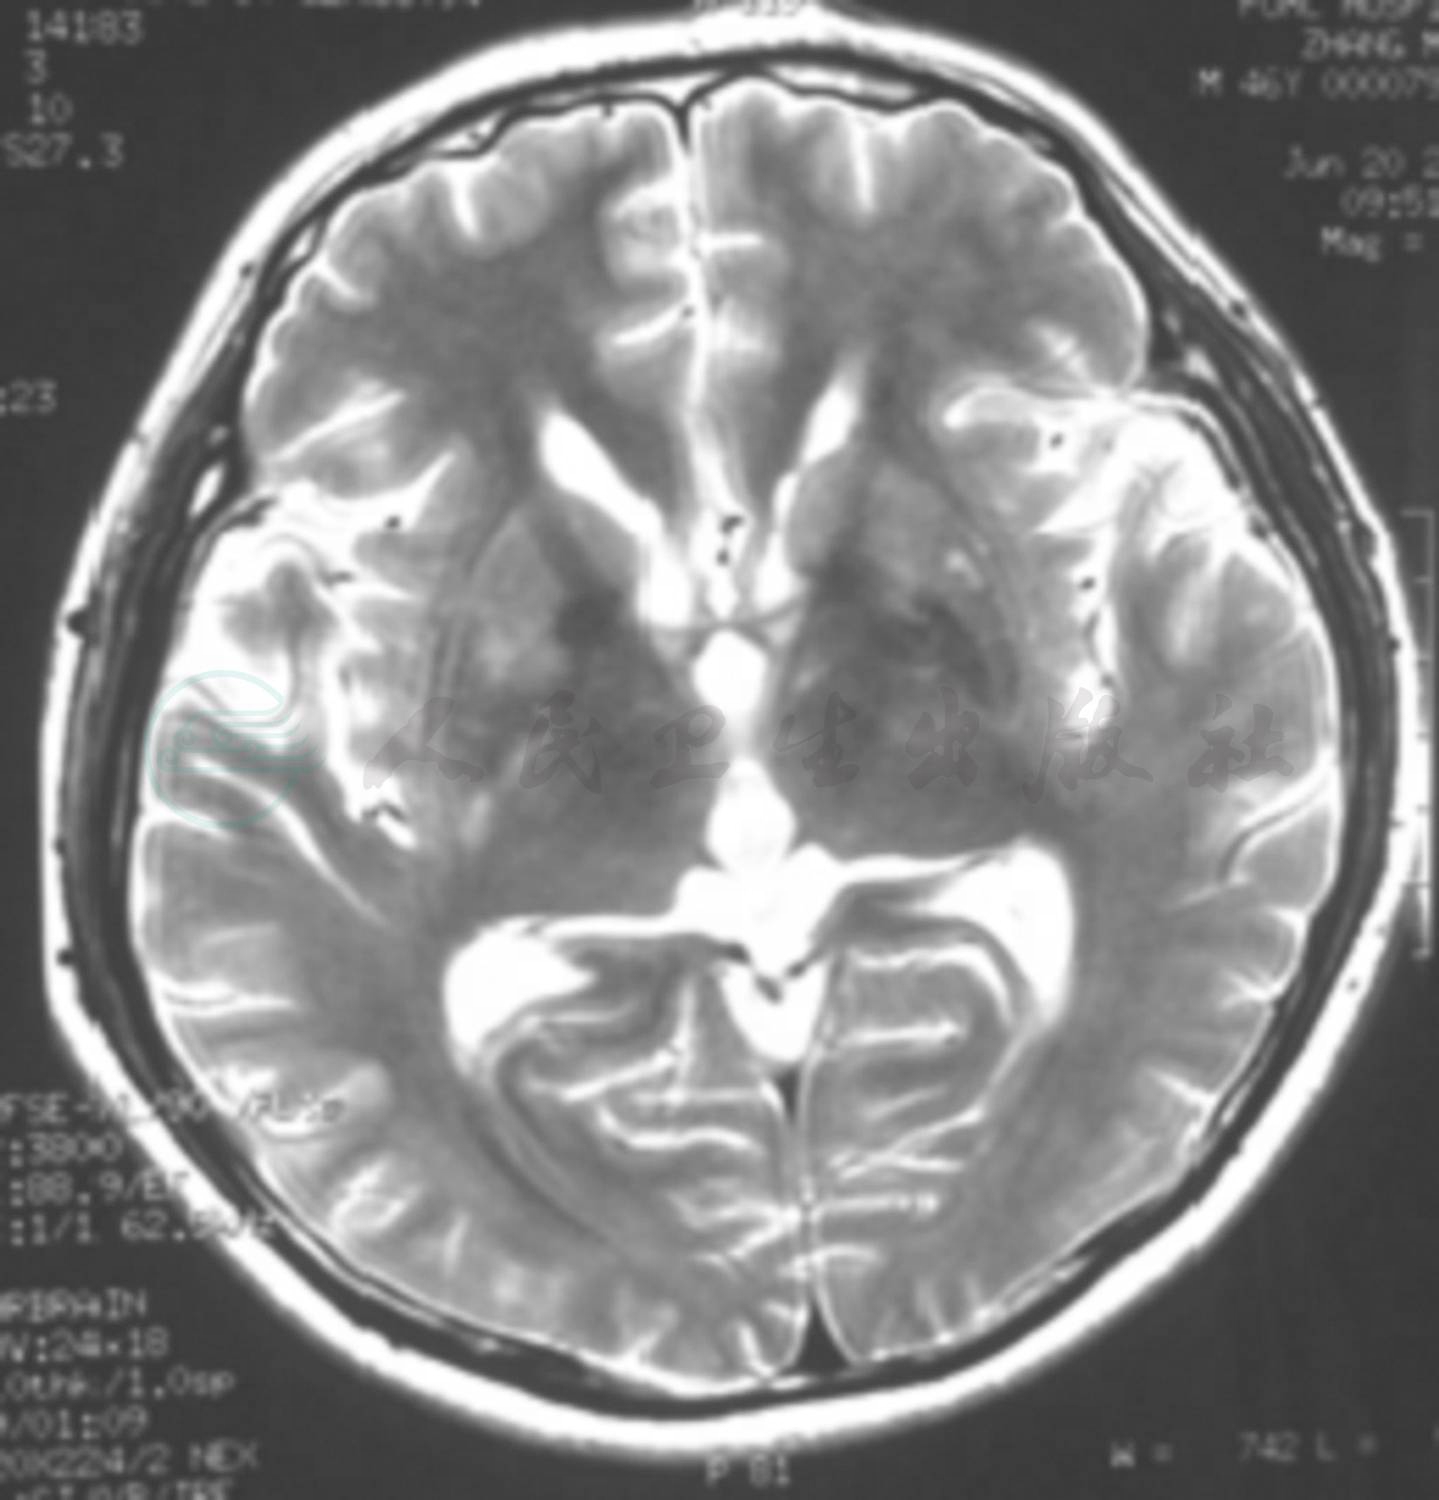

图1 患者头部MRI检查

a.横断面T2WI序列可见双侧基底节区,额颞叶皮质及皮质下多发散在长T2信号,边界模糊,病灶新旧不等;b.增强扫描无强化

9个月前(2006年10月)患者无任何原因出现全身大关节疼痛,非对称性,部位不固定,外院实验室检查“红细胞沉降率增快,血清C反应蛋白水平升高”,但抗核抗体等项免疫学指标均呈阴性,考虑为“反应性关节炎”,经对症治疗后病情好转。8个月前患者出现双眼红肿、胀痛并伴轻微头痛,但无流泪、畏光等症状,当地医院考虑为“结膜炎”,予地塞米松5mg/d,静脉滴注,3天后改为口服泼尼松10mg/d口服,关节疼痛症状减轻,但双眼红肿无改善并呈渐进性加重,由于“眼压较高”考虑“巩膜炎”而将口服泼尼松剂量增至40mg/d,治疗7天后双眼红肿症状有所好转,泼尼松口服剂量逐渐减至10mg/d维持治疗。其间患者腹部出现环形红色斑疹,无瘙痒、脱屑,并逐渐扩展至胸部、背部、颜面部和四肢,伴瘙痒,3~4天后未予治疗逐渐消退,遗留色素沉着。4个月前(2007年2月)无明显诱因患者出现活动时双手抖动,但无持物不稳;3个月后(2007年3月)出现午后持续发热,体温最高达38.5℃,伴乏力及头部持续性胀痛、记忆力减退(以近记忆力减退为主),并两次在夜间出现“谵妄”。外院头部MRI检查显示双侧岛叶、海马回、双侧基底节区及半卵圆区多个小片状长T1、长T2信号,增强扫描无强化(图1)。腰椎穿刺检查脑脊液压力为210mmH2O,白细胞计数42×106/L,单个核细胞70%,多核细胞30%,脑脊液蛋白0.630g/L,葡萄糖和氯化物正常;抗酸和墨汁染色,脑脊液细胞学未见肿瘤细胞,脑脊液细菌涂片等均无异常发现。血白细胞计数16×109/L、中性粒细胞比例0.91,结核分枝杆菌抗体(TB-Ab)阴性,EB病毒抗体(EBV-Ab)检测呈阳性反应。考虑“病毒性脑炎”给予更昔洛韦、头孢类抗生素(具体剂量不详)、地塞米松10mg/d静脉滴注,治疗10天后症状明显好转出院,但记忆力无改善,仍以口服泼尼松10mg/d维持治疗。出院后约2周患者再次出现低热,体温约为37.5℃,伴乏力,咳嗽、咳痰,双手关节游走性疼痛,伴红、热但无肿胀,同时出现“谵妄”。当地医院实验室检查显示:血常规,白细胞计数14.90×109/L,中性粒细胞比例0.84;红细胞沉降率20mm/h,结核菌素纯蛋白衍生物(PPD)皮肤试验呈阴性反应,抗可提取性核抗原(ENA)抗体、免疫球蛋白定量、蛋白电泳和甲状腺功能检测均于正常范围;腰椎穿刺检查脑脊液压力为130mmH2O,白细胞计数2×106/L,蛋白定量0.64g/L。脑电图检查未见明显异常;头部MRI扫描病灶依旧存在,无强化表现,提示脑内异常信号,炎性或血管炎性改变。遂按照“病毒性脑炎”对症治疗,病情好转后出院。出院后继续口服激素泼尼松7.50mg/d,约1周后患者再次出现“谵妄”、行走不稳,以及右耳红肿、疼痛并进行性加重情况,不伴发热,遂来我院就诊。病程中无声嘶、喘息、喉及气管软骨前压痛,无鼻塌陷及疼痛等症状与体征,无光过敏、雷诺现象、口腔溃疡及外阴溃疡等现象。患者自发病以来兴趣减退,入睡困难。大小便正常。体重无明显变化。

该患者为中年男性,急性发病,亚急性病程,病情呈波动性变化,发病初期主要表现为系统性疾病症状,曾在其他医院先后被诊断为“反应性关节炎”“巩膜炎”和“右耳郭软骨膜炎”等,就诊期间还出现皮肤损害。近4个月来反复发热及神经系统症状,如头痛、发热、记忆力减退和精神行为异常等症状。病程中及入院后实验室检查白细胞计数、红细胞沉降率及血清C反应蛋白水平等炎性指标均显著升高;多次脑脊液检查提示白细胞计数、蛋白定量轻度升高,符合淋巴细胞炎性反应。头部MRI扫描显示双侧额叶皮质下、双侧基底节区、双侧侧脑室旁、内侧颞叶斑片状长T2异常信号。定位诊断:可将患者记忆力减退、精神行为异常和高级智能活动下降(定向力、记忆力、计算力等)等症状定位于双侧额颞叶;而四肢肌张力增高、不自主运动则定位在双侧基底节锥体外系。结合影像学检查病灶所在脑区,可以解释患者目前的临床症状及体征。另外,对于全身多系统损害表现,包括皮肤陈旧性色素沉着、眼结膜溃疡、耳郭发红等,考虑全身系统性受累。定性诊断:首先应考虑中枢神经系统炎症性疾病,包括感染性及非感染性炎症。根据患者亚急性病程,临床表现为发热、头痛、记忆力减退、精神行为异常等,首先,应排除病毒性脑炎的可能。但患者病程较长,约6个月,且病情反复波动,经抗病毒治疗病情仍有反复并呈渐进性加重,说明抗病毒治疗效果欠佳,此亦不符合病毒感染自限性之特点。其次,该患者影像学呈现颅内广泛性病灶,对于灰、白质并无太多的选择性,与单纯疱疹病毒性脑炎的典型灰质受累、额颞叶为主的出血坏死影像学图像不相符;同时入院后脑电图检查亦未发现典型的颞叶或以颞叶为中心累及额叶的周期性放电,因此均不支持病毒性脑炎的典型表现。对于非感染性炎性疾病方面,应注意与中枢神经系统炎性脱髓鞘性疾病急性播散性脑脊髓炎(ADEM)相鉴别。由于该患者的病程及影像学表现与急性播散性脑脊髓炎的急性发病、单相病程、白质受累为主和发病前多有感染或疫苗接种史不符,故以上两种疾病均不支持。目前,患者有多系统及脏器受累的临床表现,且先于神经系统症状出现,支持其原发病为全身系统性疾病而神经系统损害仅为其相应表现的诊断。鉴于患者在整个病程中先后出现眼、耳、关节等多器官或系统受损,并以软骨炎为特异性表现同时伴发中枢神经系统损害,故应首先考虑复发性多软骨炎伴中枢神经系统炎性病变;建议进行耳郭病理活检证实。

患者为中年男性,亚急性发病,病程6个月余,病情反复;临床主要表现为关节疼痛,巩膜炎,皮疹,右耳郭软骨膜炎,听力减退、耳鸣及神经系统损害等多系统受累。实验室检查红细胞沉降率和血清C反应蛋白升高,免疫学、肿瘤标志物及感染指标均呈阴性,脑脊液检测提示慢性炎性改变;头部MRI检查显示双侧岛叶、海马回、双侧基底节区及半卵圆区广泛病灶;糖皮质激素治疗有效。根据其非侵蚀性、血清阴性多关节炎;眼部炎症(结膜炎、巩膜炎);耳蜗或前庭损害所致耳鸣、听力下降,耳郭软骨炎;以及激素治疗有效等表现,诊断首先应考虑复发性多软骨炎,但该病累及中枢神经系统者鲜见,国外已有相关报道,考虑可能与软骨蛋白多糖发生反应的Ⅱ型胶原蛋白抗体与神经系统(神经内膜、脑内小动脉中层及内膜)发生交叉反应有关。